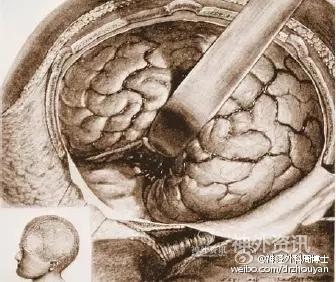

DANDY使用额颞开颅显露鞍区及鞍旁的病变。请注意,广泛的大范围的暴露导致了脑表面不可避免的损伤。20世纪二三十年代,这种大范围的开颅方法是必须的,因为这可以将更多的光线带入深部的手术视野,以利于操作粗大的手术器械。那时,Dandy在做垂体瘤手术时,需要牺牲掉左侧的视神经来获得肿瘤切除时所需要的光线照明。

Dandy在1938年提出了用于显露鞍旁区域的所谓的“垂体入路”。这个方法的皮肤切口和开颅范围较以往明显缩小。图片展示的是第一例动脉瘤夹闭术,由于局部压迫的因素,导致术后动眼神经麻痹。